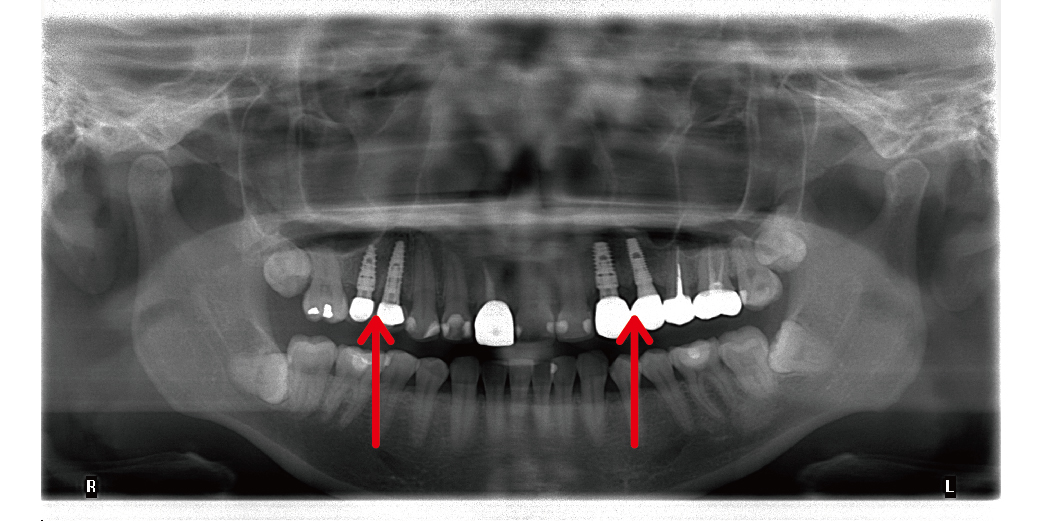

從環口X光可以看出,以植牙方式重建上顎4顆,重建咬合與美觀

植牙後追蹤,從根尖片可以看出,骨頭與植體已完成骨癒合